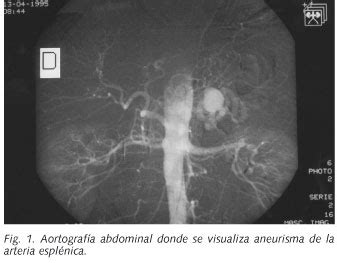

Aneurismas de la Arteria Esplénica

Los aneurismas de la arteria esplénica son los aneurismas de origen visceral más comunes en el abdomen. Su morfología es generalmente sacular y pueden complicarse con rotura espontánea. En TC sin contraste, se observan como lesiones hipodensas con calcificaciones periféricas y realce precoz tras contraste, a menos que estén trombosados.